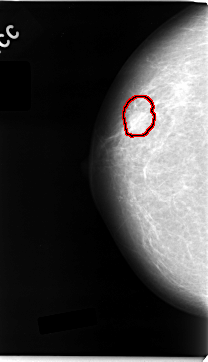

C_0035_1.RIGHT_CC

FILE: C_0035_1.RIGHT_CC.OVERLAY

TOTAL_ABNORMALITIES 1

ABNORMALITY 1

LESION_TYPE MASS SHAPE OVAL MARGINS MICROLOBULATED

ASSESSMENT 5

SUBTLETY 5

PATHOLOGY MALIGNANT

TOTAL_OUTLINES 1

BOUNDARY